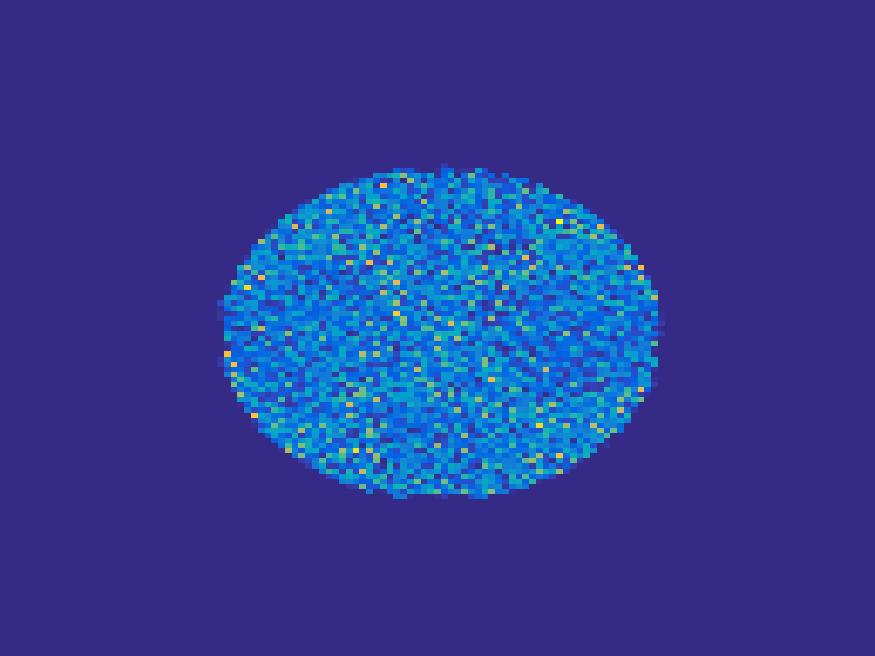

Figure 8 and 9 show the results of the ellipse and rat phantom with Poisson noise. Since the number of projections is very limited and the corruption by Poisson noise, the reconstruction by both FBP and EM (with updating basis) are not satisfactory, while the proposed method is capable to reconstruct the main structure of the images faithfully.

In order to test the performance of the proposed method in a more realistic scenario, we perform a Monte Carlo simulation for dynamic SPECT imaging. First, we created a phantom image consisting of three circles as region of interests, shown in Figure 13. The TAC over a time period of 90 time steps of the outer and the two inner circles were displayed in 13(b).

For each single frame, the photon counts is a probability proportional to the concentration in every region. The events are detected by a virtual double heads gamma camera rotating around the patient by degrees per time step, which consists of detector bins. Every simulated decay event is projected and counted by the corresponding detector bin.

We set the number of events counted by the detector as and ) times the average concentration in one pixel of two different tests. The signogram images the count in each bin of two settings are shown in Figure 14.

Based on the sinogram data, we compare the proposed method with the alternating EM algorithm. The results for both test cases are shown in Figure 15. We can see that for the case of a low count number, the proposed method is able to reconstruct the regions properly. Within a number of iterations, the algorithm presents a reasonable reconstruction of the region of interest and the corresponding regional tracer concentration curves.